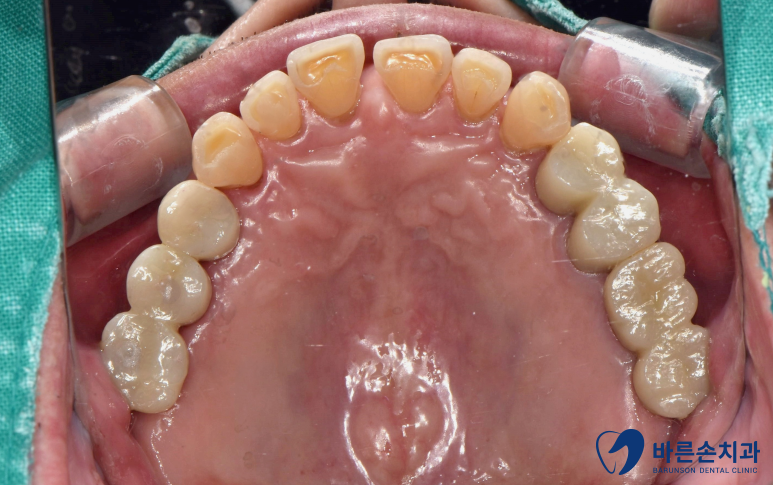

치료가 다 끝난 사진입니다!

상실되어있던 치아들이 전부 생기게 되었고

치아색 보철로 내 치아처럼 자연스럽게 제작되었습니다

이제 아래 치아와 전부 맞닿게 되니까

식사 하시기 훨씬 편해지실겁니다!